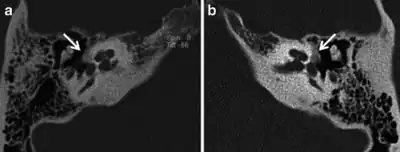

Images of the right a) and left (b) hypodense demineralised plaques arrow consistent with fenestral otosclerosis

CT scan of otosclerotic focus in the anterior footplate

Imaging is usually not pursued in those with uncomplicated conductive hearing loss and characteristic clinical findings. Those with only conductive hearing loss are often treated medically or with surgery without imaging. The diagnosis may be unclear clinically in cases of sensorineural or mixed hearing loss and may become apparent only on imaging. Therefore, imaging is often performed when the hearing loss is sensorineural or mixed.

A high-resolution CT shows very subtle bone findings. However, CT is usually not needed prior to surgery.

Otosclerosis on CT can be graded using the grading system suggested by Symons and Fanning.[16]

- Grade 1, solely fenestral;

- Grade 2, patchy localized cochlear disease (with or without fenestral involvement) to either the basal cochlear turn (grade 2A), or the middle/apical turns (grade 2B), or both the basal turn and the middle/apical turns (grade 2C); and

- Grade 3, diffuse confluent cochlear involvement (with or without fenestral involvement)